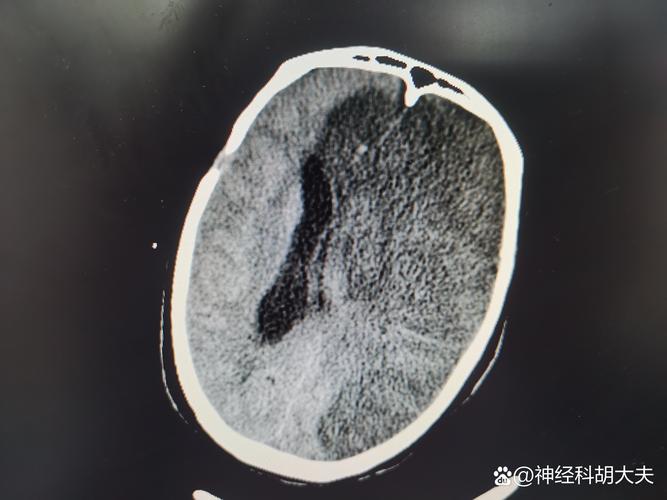

- 脑CT平扫:这是脑梗患者最常做的检查,它主要是通过X射线观察脑组织是否有出血、梗塞、肿瘤等结构性病变,这个检查过程不需要注射造影剂,因此没有空腹的必要。

(图片来源网络,侵删)- 对于急性脑梗塞患者,治疗的关键在于“时间窗”,在发病后的4.5小时内(部分患者可延长至6小时),如果能及时使用溶栓药物,可以最大限度地挽救濒临死亡的脑细胞,显著减少后遗症。